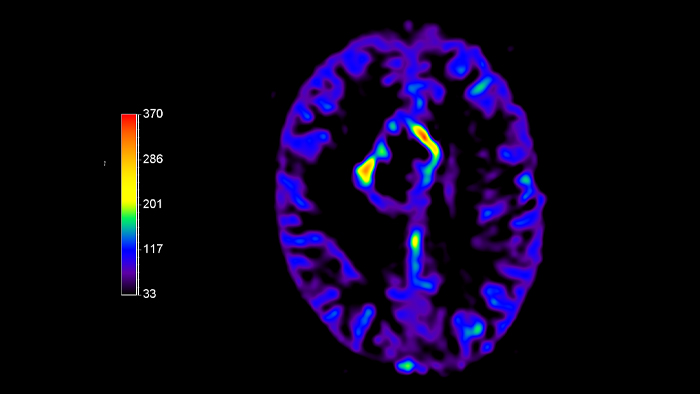

pCASL

Clinical application pCASL

Clinical Area

Brain